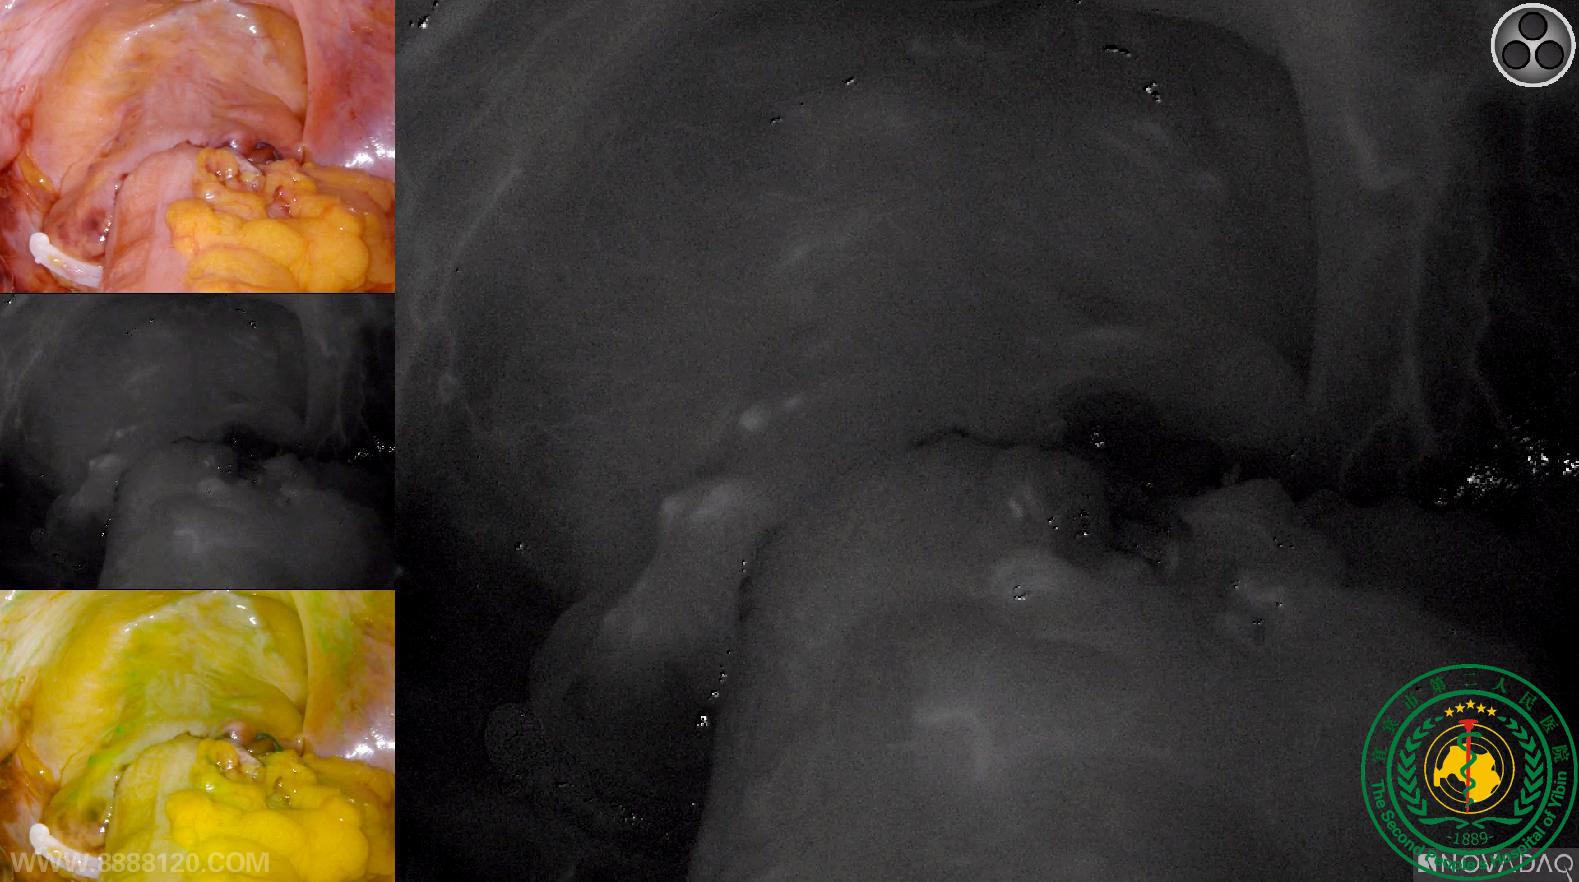

我院胃肠外科成功开展四川省第一例荧光腹腔镜直肠癌NOSES手术

我院胃肠外科成功开展四川省第一例荧光腹腔镜直肠癌NOSES手术16559

宜宾市第二人民医院 图文